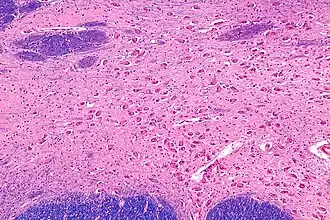

Neurons of the nucleus basalis are particularly vulnerable in age-related neurodegenerative diseases such as Alzheimer's disease,[3] Parkinson's disease, and several others.[2] The resulting decrease in acetylcholine in the brain is thought to contribute to the decline in mental function of affected patients.[3][2] For this reason, most currently available pharmacological treatments for dementia focus on compensating for faltering function of the nucleus basalis through artificially increasing acetylcholine levels. Because many other systems also are compromised in neurodegenerative diseases, the benefits of selectively increasing cholinergic function are limited.[12]